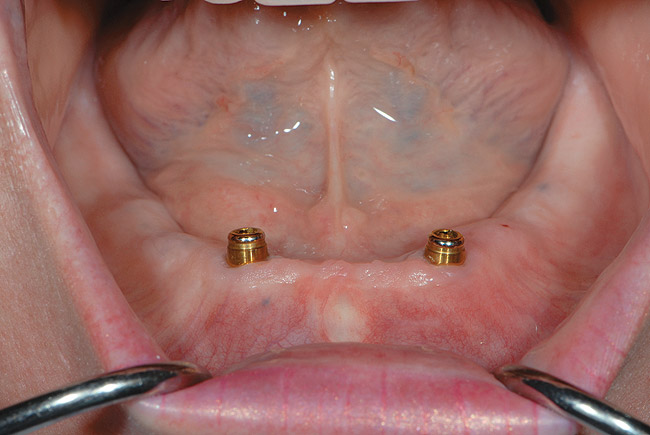

Figure 5  Locator abutments placed on implants can also be used for an implant-assisted prosthesis.

Figure 5

When dental implants were introduced by Brånemark, they were intended primarily for the completely edentulous patient, specifically the edentulous mandible. The initial prosthesis was a fixed restoration commonly referred to as a fixed bone anchored bridge. That particular prosthetic design is now the fixed-detachable hybrid prosthesis and has been highly successful for both the implants and prostheses.12,13 Implants have also been used for overdenture restorations14 and can be implant-assisted or implant-supported. With implant-assisted prostheses, the implants and mucoperiosteum share the forces of occlusion. A simple two-implant overdenture, either a Hader Bar® (Sterngold™, Attleboro, MA) or Locator® abutment (Zest Anchors, Escondido, CA), are examples of implant-assisted overlay prostheses and are always a removable restoration (Figure 4 and Figure 5). With implant-supported prostheses, the forces of occlusion are borne solely by the implants. This prosthesis can be an overlay prosthesis or a fixed restoration. Milled bar restorations, overdentures with bar substructures, and metal ceramic restorations attached to implant abutments by either screws or cement are examples of implant-supported restorations. One of the primary benefits of using dental implants in edentulous patients is the preservation of the residual bone, which will provide a better opportunity for future successful prosthetic restorations.